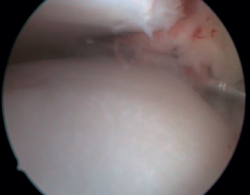

Bony AAI due to osteophytes has also been linked to the presence of chronic instability. It has been postulated that altered joint kinematics secondary to ligament insufficiency favors the development of osteophytes in the anterior region of the tibia and talus(36,37). Recent studies have questioned the theory of repeated capsular traction as the origin of osteophytes in sports(38), as it is easily demonstrated that osteophytes are located intra-articular within the capsular insertion, in the context of ankle arthroscopy (Figure 2). Therefore, ankle dorsiflexion arthroscopy is essential to safely resect osteophytes without damage to the capsule or overlying structures, whereas the classical traction technique (invasive or otherwise) would make resection extremely difficult, and is thus not recommended nowadays for routine use(3,39). Vega distinguished between two types of osteophytes(3), according to whether they are caused by repetitive trauma (peak-shaped) or instability (visor-shaped). The concept of micro-instability is associated with repetitive micro-trauma, which could be the origin of osteophytes with this characteristic morphology (Figure 3).

Resection of the osteophyte is performed by displacing from the top, and gradually reducing it until the joint zone is reached (Figure 2). A basket forceps can be used to resect the area closest to the joint (Figure 5). It is often useful to exchange the viewing and working portals in order to visualize and completely resect the osteophytes. In the case of soft tissue impingement, a 3.8 or 4 mm synoviotome is usually sufficient. The vaporizer is useful in the case of compact impingements, typical of post-traumatic conditions or re-interventions, and also for delimiting the bony part of the osteophyte before resection.

Figure 2. Anterior tibial osteophyte. A: in dorsiflexion the capsule separates from the osteophyte allowing its resection (B) through reaming.